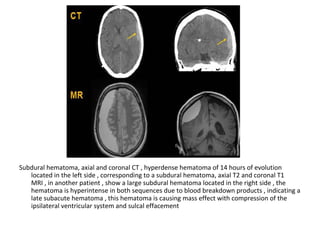

MRA with non-visualization of the left transverse sinus, since the venous anatomy is

variable, this can be due to absence of the transverse sinus or thrombosis, the T1

clearly demonstrates, that there is a transverse sinus on the left, so the MRA

findings are due to thrombosis

The same patient , CT shows the dense thrombosed transverse

sinus (yellow arrow) , the FLAIR shows the venous infarction

in the temporal lobe